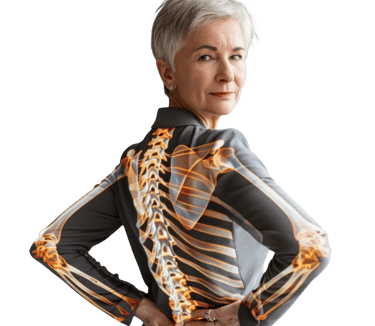

Bone Health Support

A safe technology that boosts bone cell activity and helps increase bone strength, making it ideal for people with low bone density or osteoporosis.

Targets the source of pain by improving cell function, reducing inflammation, and restoring comfortable, natural movement.

When pain, stiffness, or injury disrupt your life, real relief should target the source not just cover up the symptoms. MBST offers a different path. By acting directly on the cells where damage begins, it aims to ease pain, reduce inflammation, and improve mobility for people dealing with musculoskeletal issues, chronic discomfort, or long-term conditions.

MBST uses precise magnetic resonance signals to create conditions that support healthy cell activity and natural repair. When cells operate the way they’re meant to, they can better restore balance, regenerate tissue, relieve discomfort, and reduce inflammation.

Chronic inflammation can interrupt these processes and slow down healing. By helping to bring this inflammation under control, MBST promotes more efficient cellular function, allowing your body’s own repair mechanisms to work stronger and deliver long-lasting recovery.